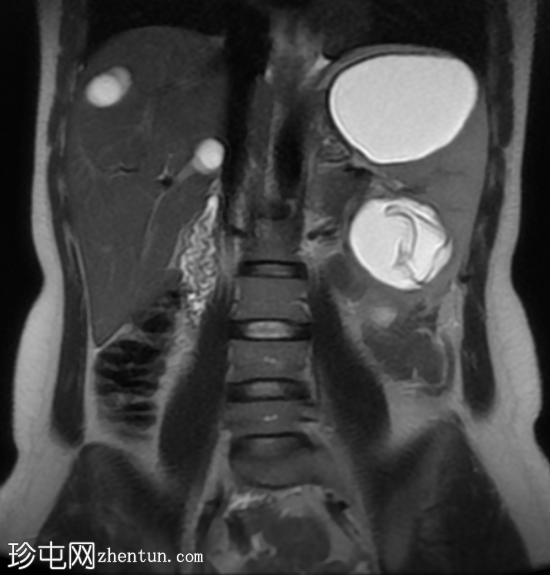

冠状位

T2加权像

肝脏肿大,可见多发性双叶肝囊肿。

脾脏肿大,可见多发性大囊肿,内层脱离。

肝脾包虫囊肿的典型

影像

学表现。